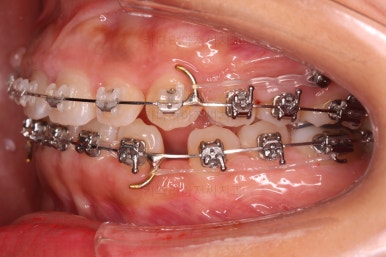

이제는 아래 앞니가 3개이기 때문에 생기는 중앙선의 문제, 치아 갯수의 문제를 맞춰나가기로 했습니다.

계획은 오른쪽 아래 송곳니 ~ 어금니 모든 치열을 앞쪽으로 밀어줘 아래 앞니를 마치 4개인 것처럼 만드는 것입니다.

위쪽은 미니스크류 위치를 바꿔줘 교합을 맞춰주고요.

아래쪽은 마찬가지로 미니스크류를 비대칭으로 식립해서 어금니를 당겨줍니다.

계속 당겨줍니다.

위아래 치열의 중앙이 서서히 맞아지는 느낌이 드시나요?

조금만 더 하면 되겠네요.